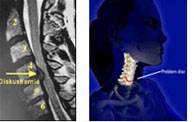

Boyun Fıtığı:

Boyun fıtığı, her iki boyun omuru arasında yastık görevi yapan disk dokusunun omurilik ve kola giden sinirlere doğru taşmasıdır. Basının büyüklüğü ve etkinliğine göre boyun ve kol ağrısı, kol kaslarında kuvvet kaybı, ellerde his kusuru, uyuşma ve beceriksizlik görülebilir. Eğer omur iliğe doğru bası olur ise yürüme zorluğu, bacaklarda kuvvetsizlik ve idrar şikayetleri de görülebilmektedir.

Diskte dejenerasyon, Kireçlenme:

Yaşın ilerlemesi, omurganın kötü kullanılması sonucu kemik yapıda, bağlarda ve disklerde yıpranma başlar. Jöle kıvamındaki disk keçeleşir, kuvvet emme özelliği ve esnekliğini kaybederek çöker. Kemiğin kalsiyum içeriği azalır. Vücut doğal tepkisi olarak bu yıpranmış dokuları kireçlendirir. Oluşan yeni kemikçikler, taşlaşmış bağlar ve daralmış disk mesafeleri sinirlere bası yaparak boyun, kol ve genel vücut ağrısına sebep olabilmektedir. Omurilik basısı yaparak el ve ayaklarda uyuşma, kuvvetsizlik oluşabilmektedir. Mutlak tedavi edilmelidir.